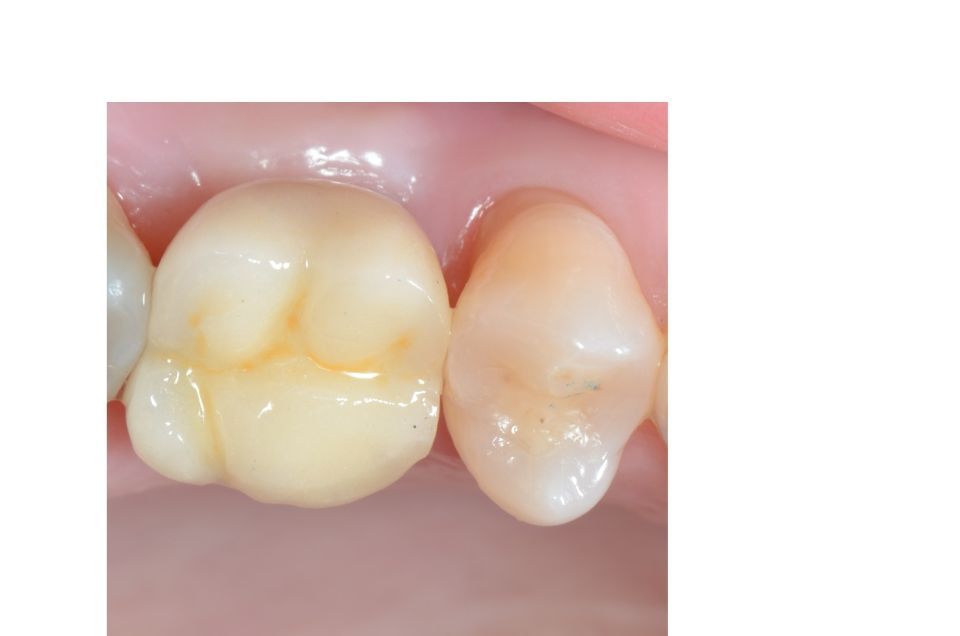

Odontologia restauradora/conservadora

Tal com el seu nom indica, tracta de conservar mitjançant la reconstrucció de les dents que s'han cariat o s'han fracturat, que han patit un traumatisme o estan erosionades; per preservar la seva funció com a dent.